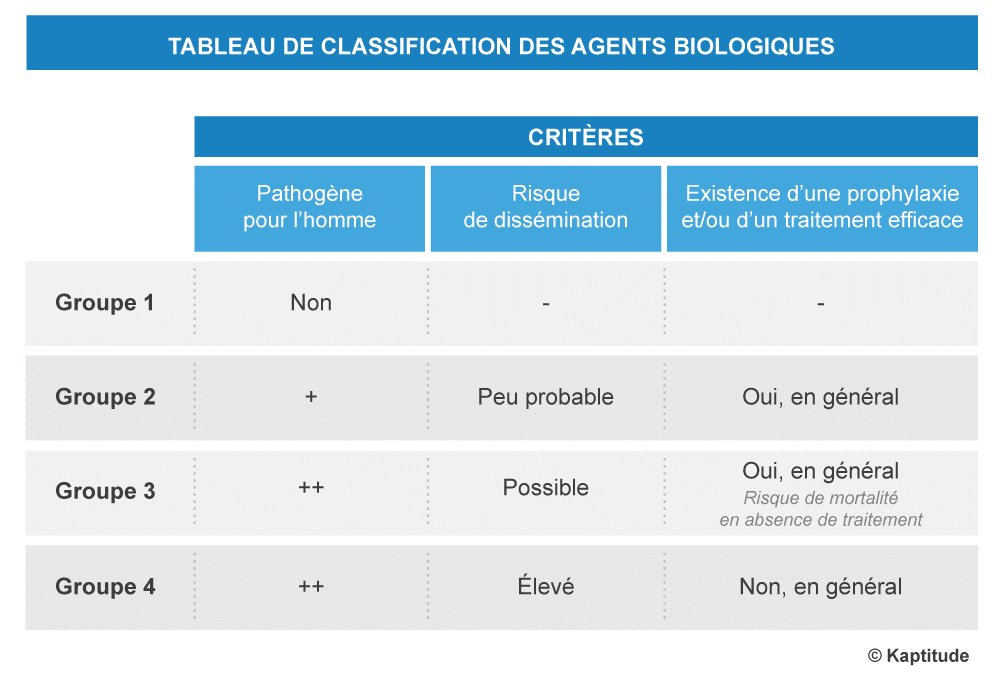

La classification des agents biologiques

La réglementation (article R4421-3 du code du travail) permet une classification des agents biologiques en 4 groupes de risques croissants, basée sur trois critères : 1) leur pathogénicité pour l’Homme, 2) le risque de dissémination dans la collectivité, et 3) l’existence d’une prophylaxie* ou d’un traitement efficace.

*Prophylaxie : ensemble de moyens destinés à prévenir l’apparition, la propagation ou l’aggravation des maladies.Les agents biologiques non-pathogènes sont classés dans le groupe 1. Il n’existe pas de liste exhaustive pour ces agents biologiques car ils sont innombrables.

Seuls les agents des groupes 2 à 4 sont pathogènes pour l’Homme.

Le groupe 2 comprend donc des agents biologiques pouvant provoquer une maladie chez l’Homme mais dont la propagation dans la collectivité est peu probable. Pour les agents biologiques de ce groupe, il existe généralement une prophylaxie et/ou un traitement efficace.

Le groupe 3 comprend les agents biologiques pouvant provoquer une maladie grave chez l’Homme. Leur propagation dans la collectivité est possible, mais il existe généralement une prophylaxie et/ou un traitement efficace.

Enfin, le groupe 4 comprend également les agents biologiques pouvant provoquer une maladie grave chez l’Homme et leur propagation dans la collectivité est élevée, de plus il n’existe généralement ni prophylaxie ni traitement.

Il faut noter que l’appartenance à l’un de ces groupes n’est pas figée ; en fonction de l’avancée des connaissances, la classification d’un agent biologique donné peut être amenée à varier.

Lorsque vous travaillez avec un agent non encore classé, il est recommandé de ne pas le considérer par défaut comme non dangereux (groupe 1). Sa classification doit résulter de l’évaluation basée sur les critères mentionnés précédemment.

Il est important de noter que chaque agent est classé selon l’évaluation de la pathogénicité pour une personne en bonne santé. En effet, elle peut varier selon l’état de santé de chacun (immunosuppression, grossesse, etc.). C’est pourquoi un suivi individuel de santé est réalisé régulièrement pour tout salarié exposé aux agents biologiques des groupes 2, 3 et 4.